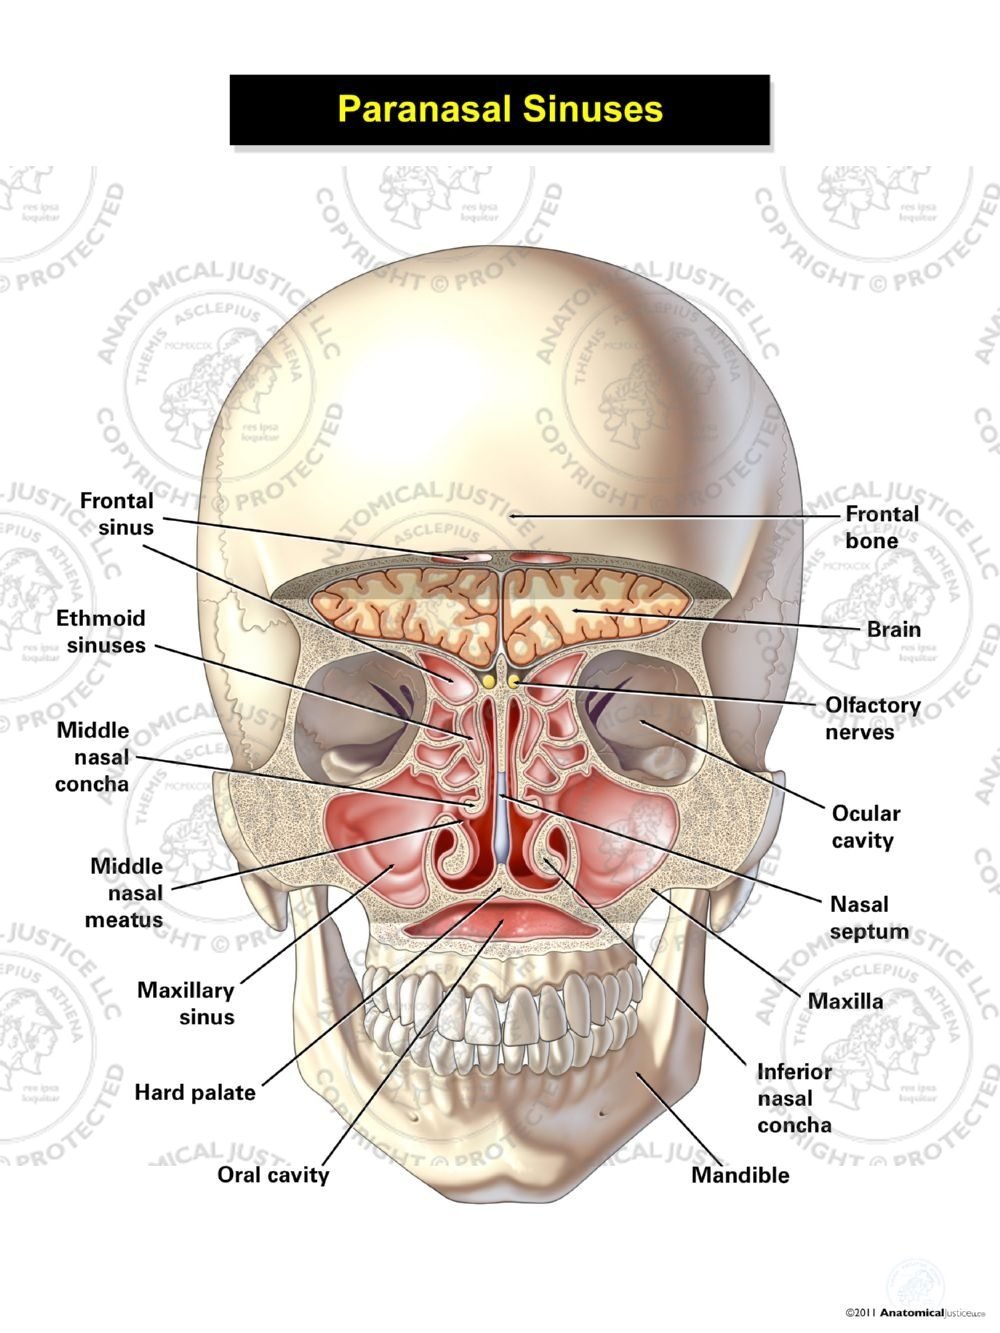

Nasal passage anatomy. Beyond the nasal valve the nasal passages are lined mostly by membranes more like the lining of the lungs called respiratory epithelium which is thin and rich in blood vessels. The sinuses are part of your nose and respiratory system. Openings into the nasal cavity.

The lateral nasal wall consists of inferior and middle turbinates and occasionally a superior or supreme turbinate bone. The turbinates consist of three ridges of thin shell like bone known as the nasal conchae. The nasal passages are lined with a membrane composed primarily of one layer of flat closely packed cells called epithelial cells.

Superior middle and inferior meatus. The nasal cavity extends from the external opening the nostrils. The nasal cavity is surrounded by a.

In bones behind your nose are your sphenoid sinuses. Anatomy of the nasal cavity. This region is divided into a labyrinth of slit like passages by multiple bony proturbances that fill the nose and act as shelves.

Role as a passage for inhaled air. Normally the sinuses are empty except for a thin layer of mucus. The ridges are named for their position.

Internally the nasal septum divides the nasal cavity into a right and left side. They connect to your nasal passages in a complex network of air flow and drainage passages. One of the functions of the nose is to drain a variety.

The external nose consists of paired nasal bones and upper and lower lateral cartilages. The nasal cavity refers to the interior of the nose. The nasal cavity is the most superior part of the respiratory tract.